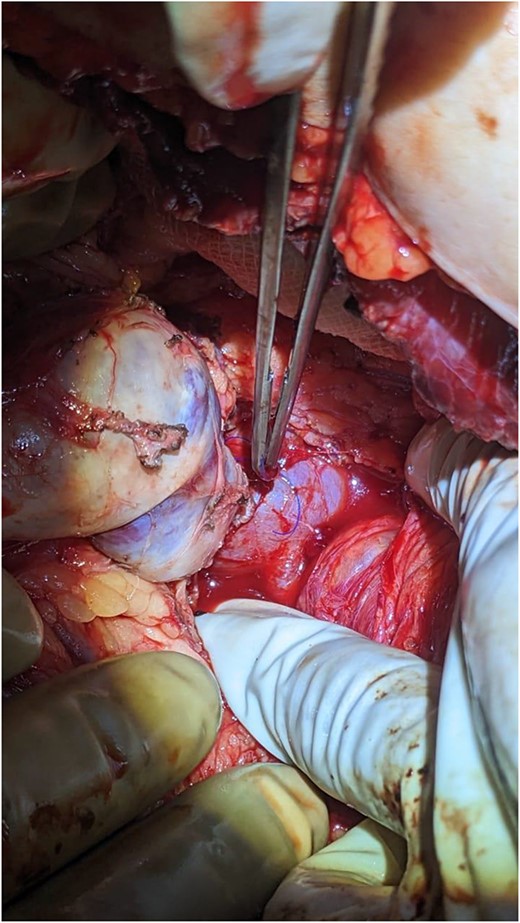

The surgical procedure involved a Chevron incision. During the operation, an enlarged and firm spleen was encountered. Multiple dilated and tortuous varices were found around the spleen involving the splenocolic, phrenicocolic, and gastrocolic ligaments. The splenic vein was also dilated and tortuous. Splenic vein dissection was affected proximal to the splenic hilum to preserve maximum length for the subsequent shunt. Following removal of the spleen, an end-to-side, central (non-selective) spleno-renal shunt was performed with polydioxanone 5/0.

The patient was monitored for vital signs, pain, and fluid balance during the immediate post-operative period. She had an uneventful recovery and was discharged on the third day after surgery (Fig. 4).